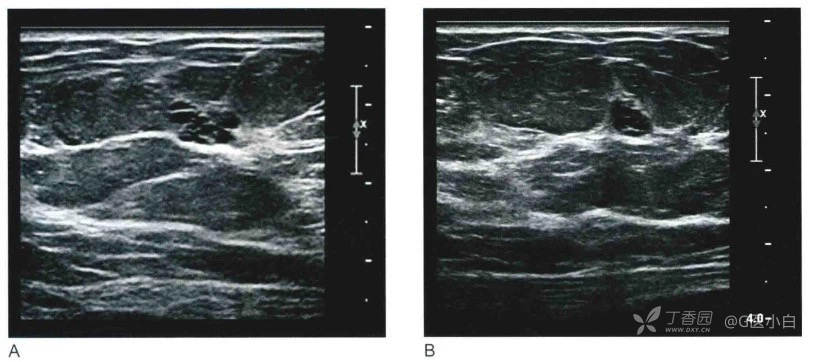

◆孤立、内部均匀低回声的复杂性囊肿。

复杂性囊肿是指含有沉积物的囊肿,沉积物的成分可以为蛋白质、细胞、血液或脓液,其常表现为均匀一致的低回声水平,无实性成分,囊壁常不易辨别,动态观察其内部回声可随体位改变而缓慢变化。

(注:评估为3类的复杂囊肿,应无附壁结节、厚分隔、后壁或其他任何可以的实性成分)